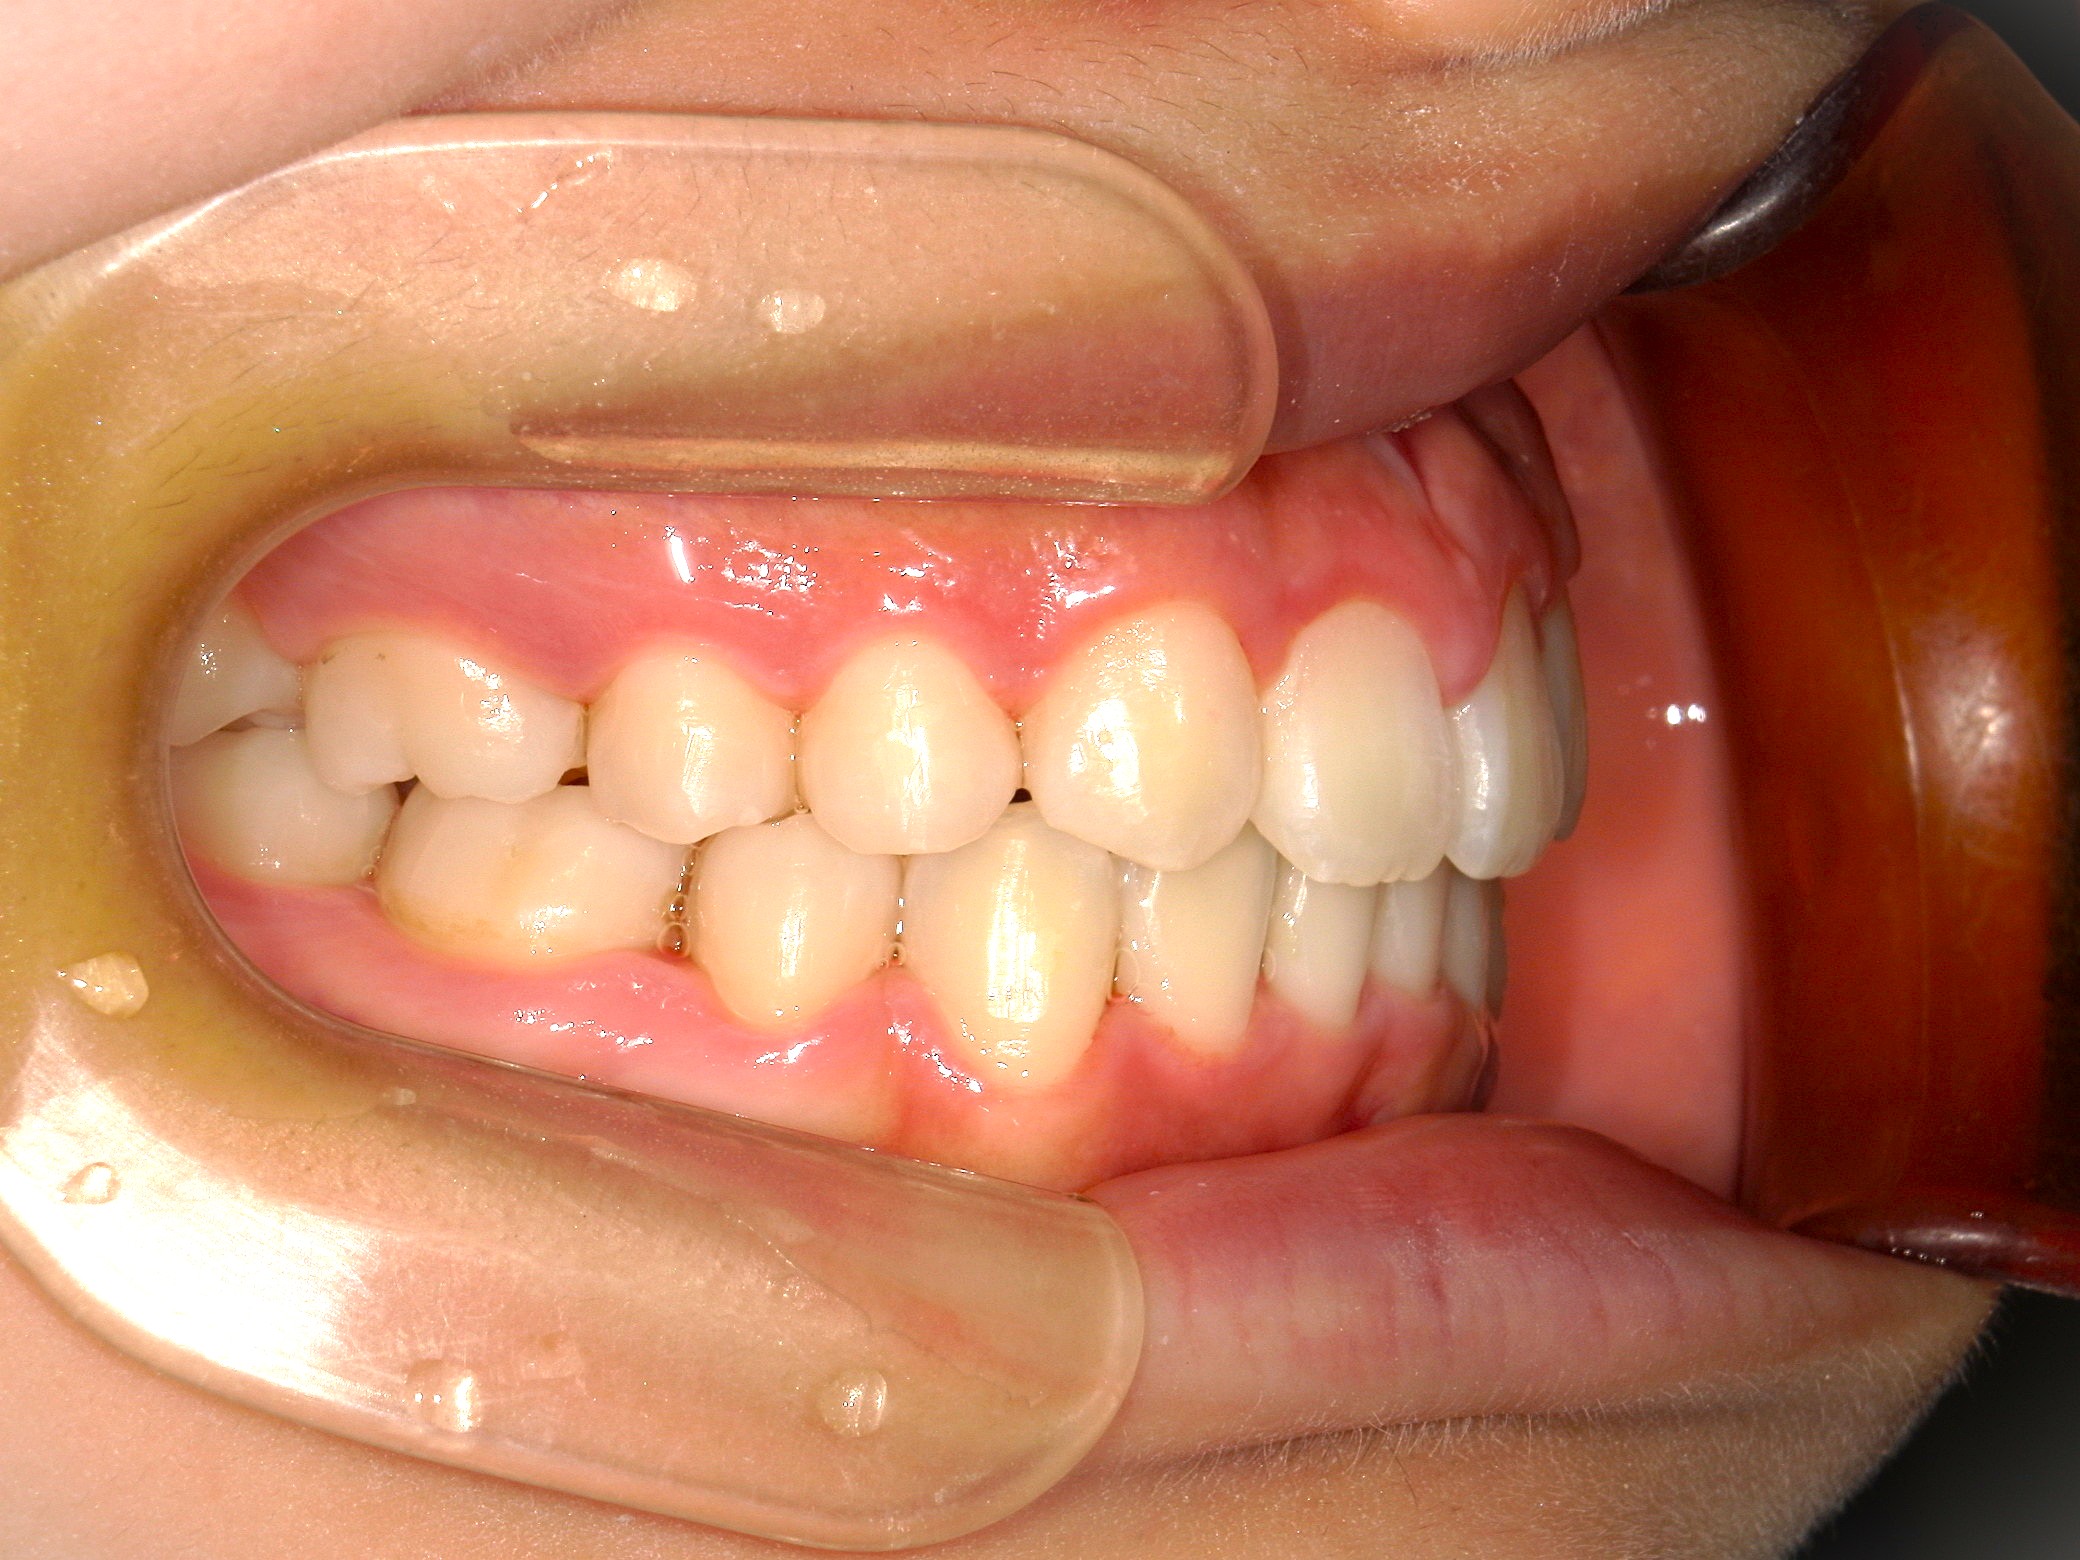

口内左

治療前

歯を並べる隙間を作るため、上下共に歯を抜いて治療を行うこととしました。

上は矮小歯を、下は横の歯を抜いて治療を行いました。

上の歯は2番の歯を犬歯で代替しているので、上下の大きさの違いが出るのですが、不自然にならないよう幅をわずかに調節して仕上げています。